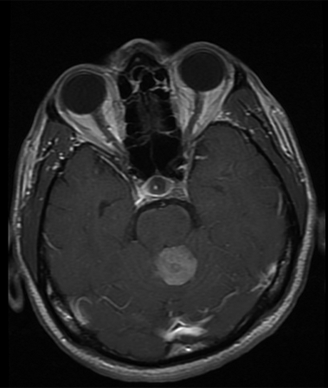

Medulloblastoma—T1 weighted post-contrast MRI image revealing an enhancing posterior fossa mass, consistent with medulloblastoma.